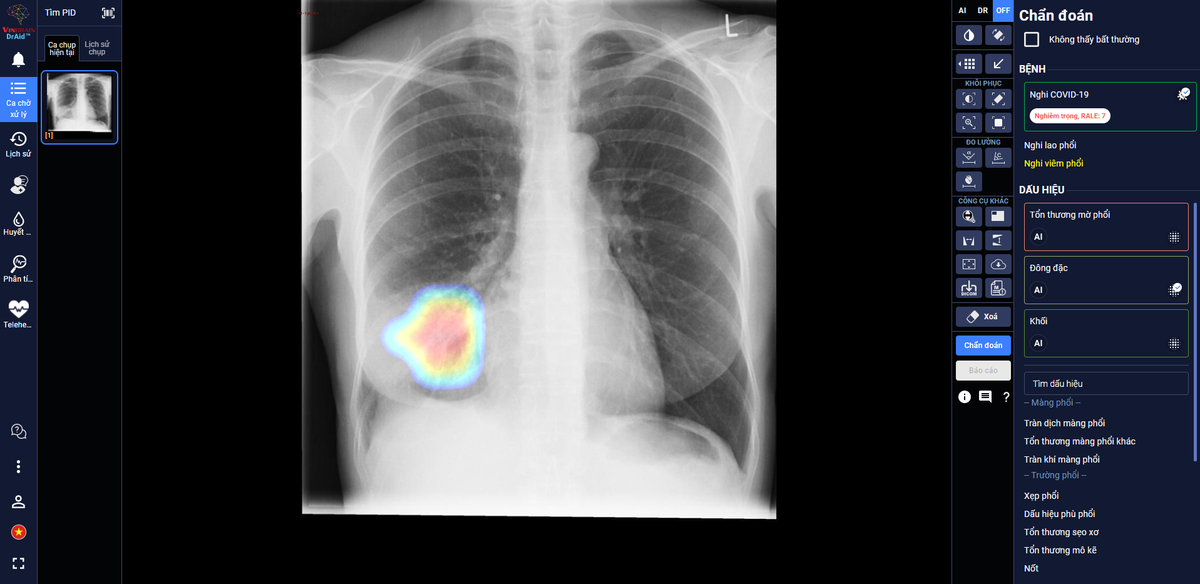

DrAid giúp bác sĩ theo dõi mức độ tổn thương phổi ở một bệnh nhân F0 trên ảnh X-quang phổi

Trong các bệnh viện thu dung điều trị COVID-19, DrAid cho COVID-19 giúp các bác sĩ đánh giá mức độ tổn thương phổi của bệnh nhân COVID-19 qua các ngày, từ đó đưa ra các chỉ định điều trị kịp thời và hiệu quả cho bệnh nhân.

Theo đánh giá của các bác sĩ tại Trung Tâm Y Tế Kỳ Anh – Hà Tĩnh, AI đã giúp đỡ các bác sĩ khá nhiều khi theo dõi tổn thương qua các ngày, nhận diện rõ ràng là tổn thương lan rộng như thế nào. Ngoài ra, AI cũng giúp bác sĩ nhận diện các tổn thương nhỏ dễ bỏ sót.